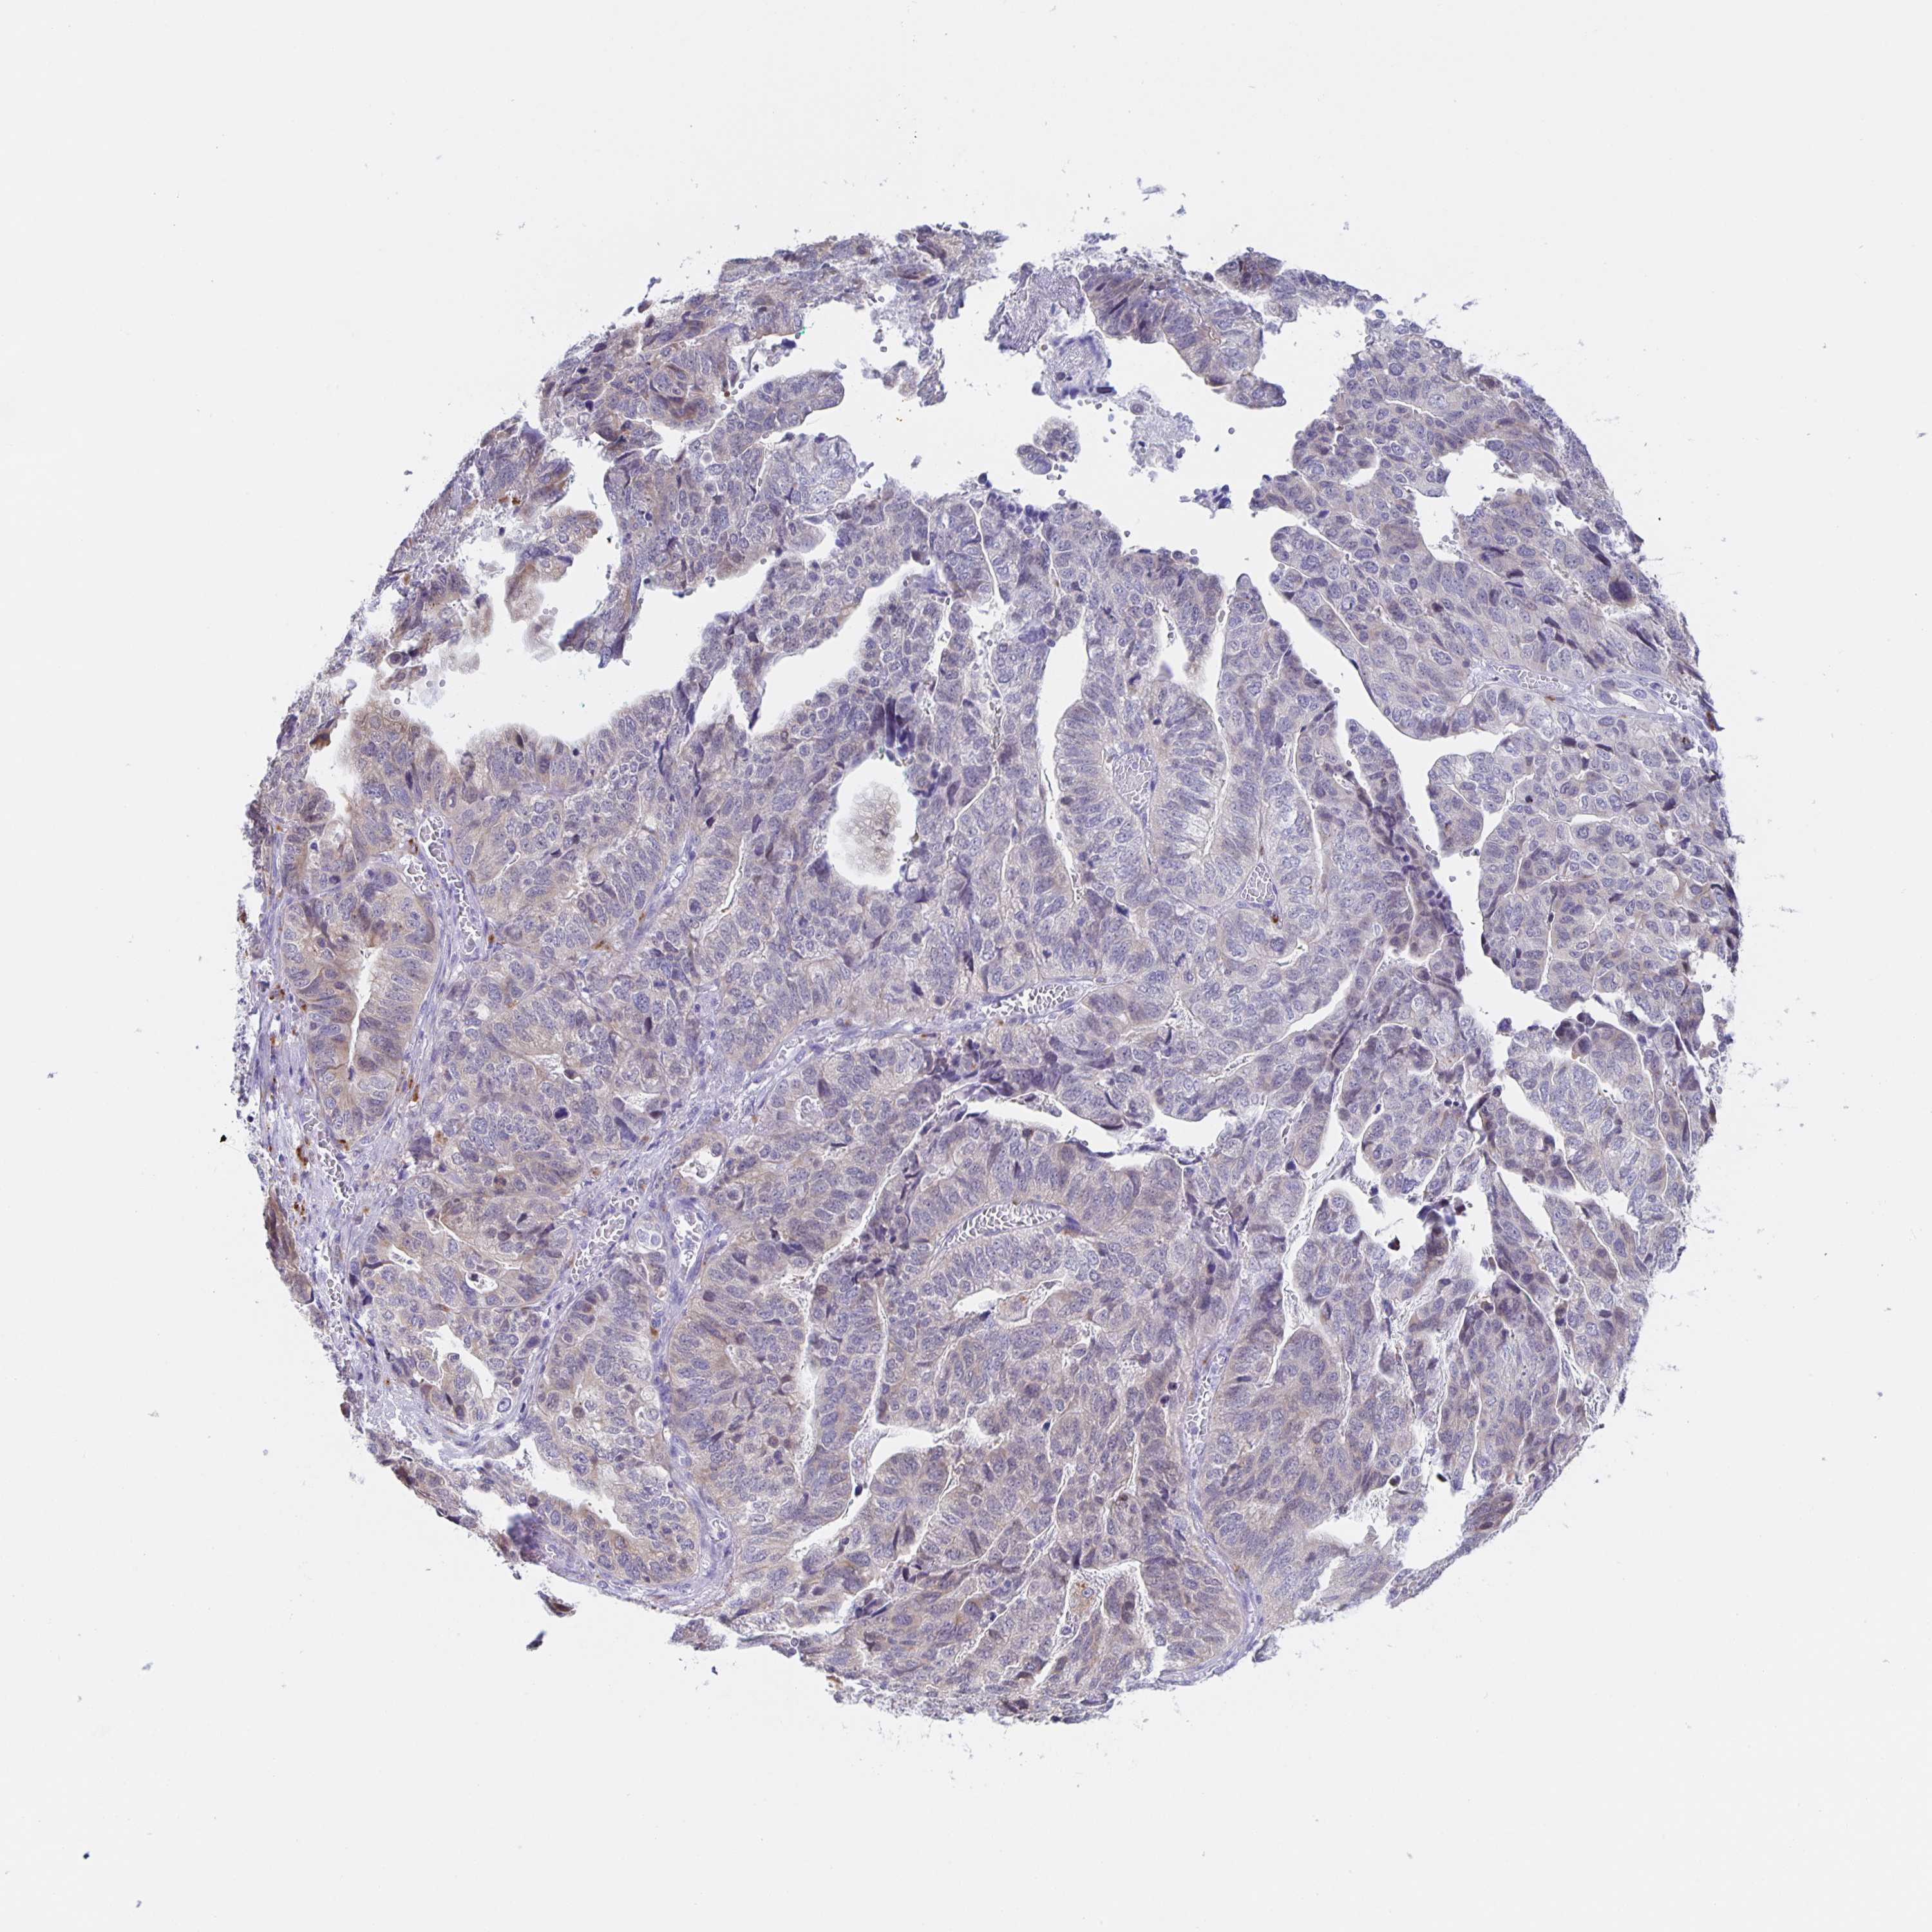

STOMACH CANCER - Protein expressioni

A mouse-over function shows sample information and annotation data. Click on an image to view it in a full screen mode. Samples can be filtered based on level of antibody staining by selecting one or several of the following categories: high, medium, low and not detected. The assay and annotation is described here.

Note that samples used for immunohistochemistry by the Human Protein Atlas do not correspond to samples in the TCGA dataset.

Antibody stainingi

Antibody staining in the annotated cell types in the current human tissue is reported as not detected, low, medium, or high, based on conventional immunohistochemistry profiling in selected tissues. This score is based on the combination of the staining intensity and fraction of stained cells.

Each image is clickable and will lead to virtual microscopy that enables deeper exploration of all samples and also displays staining intensity scores, fraction scores and subcellular localization as well as patient and tissue information for each sample.

Antibody HPA057052

Antibody CAB034892

Staining

High

Medium

Low

Not detected

Intensity

Strong

Moderate

Weak

Negative

Quantity

>75%

75%-25%

<25%

None

Location

Nuclear

Cytoplasmic/membranous

Cytoplasmic/membranous,nuclear

Adenocarcinoma, NOS